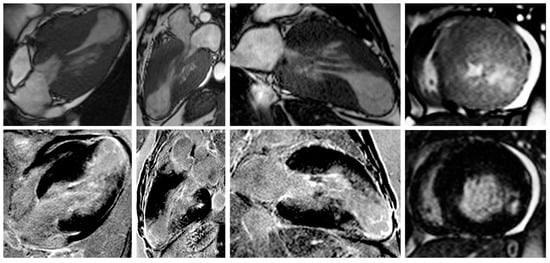

Nonetheless, due to increased temporal resolution, ability to comprehensively evaluate all heart structures and capacity to characterize myocardial tissue and unravel fibrosis, CMR has currently became the gold-standard imaging tool for diagnosing and assessing patients with HCM. CMR is able to accurately quantify heart chambers’ volumes and dimensions and also both LV and right ventricle (RV) systolic functions. Moreover, CMR is the only large-scale available noninvasive imaging tool capable of tissue characterization. This aspect has a tremendous role in patients with HCM since it can identify and accurately quantify both myocardial replacement and diffuse fibrosis and it can also exclude other infiltrative cardiomyopathies such as amyloidosis [27]. CMR summarized in Table 1. Specific cases of HCM assessed by CMR are presented in Figure 2, Figure 3 and Figure 4.

Figure 2. Contrast-enhanced CMR in a 50-year-old male patient with hypertrophic cardiomyopathy (from the own collection of the authors). (Upper row): b-SSFP cine images in two chambers, four chambers, short axis and three chambers, respectively. There is asymmetrical LV hypertrophy, with a maximum thickness of 20 mm at the basal anterior wall. The LV is not dilated and the LVEF is within normal limits (59%). There is systolic anterior motion of the mitral valve, resulting in acceleration of the systolic flow in the LV outflow tract. (Lower row): LGE imaging shows patchy myocardial fibrosis of the hypertrophied segments. Abbreviations: b-SSFP, balanced steady-state free precession; CMR, cardiac magnetic resonance imaging; LVEF, left ventricle ejection fraction; LGE, late gadolinium enhancement; LV, left ventricle.

Figure 3. Contrast-enhanced cardiovascular magnetic resonance imaging in a 32-year-old male patient with a history of hypertrophic cardiomyopathy due to a pathogenic mutation in MYBPC3 gene (c.772G>A) (from the own collection of the authors). The current findings are compatible with a phenotype of burn-out HCM. (Upper row): b-SSFP cine images in two, four and three chambers, and short axis, respectively. The LV is severely dilated (166 mL/m2) with severe systolic dysfunction (LVEF 22%). Currently, there is no LV outflow tract obstruction, although an obstructive phenotype was diagnosed 10 years before. (Lower row): LGE imaging shows extensive heterogeneous replacement myocardial fibrosis at the level of the interventricular septum, anterior and inferior LV walls, respectively. Also note the fibrosis of the papillary mitral muscles. Abbreviations: b-SSFP, balanced steady-state free precession; CMR, cardiac magnetic resonance imaging; LVEF, left ventricle ejection fraction; LGE, late gadolinium enhancement; LV, left ventricle.